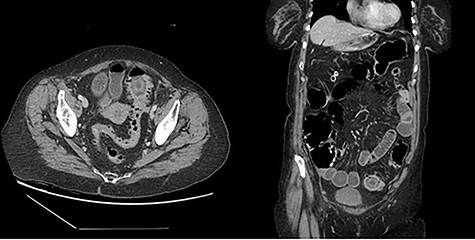

The second patient is a 69-year-old female who presented to the emergency room with complaints of obstipation and abdominal pain. She reported a 2-month history of intermittent sudden onset abdominal pain accompanied by abrupt bowel movement and nausea. At the time of presentation, she reported constipation for 5 days; she had tried fiber and suppositories without relief. Her past medical history included hypertension and irritable bowel syndrome. She had no prior abdominal surgeries or colonoscopies. Upon evaluation, she was afebrile and hemodynamically stable. Her abdomen was softly distended with localized left lower quadrant tenderness and no peritoneal signs. Her rectal exam was unremarkable. She had a mild leukocytosis of 12.9 thou/cmm. Abdominopelvic CT with intravenous contrast was obtained and revealed inflammatory stranding consistent with acute diverticulitis with a lamellated intraluminal mass in the sigmoid colon in the region of inflammation as well as pneumobilia (Fig. 4); these findings led to the diagnosis of a gallstone impaction with resulting large bowel obstruction.